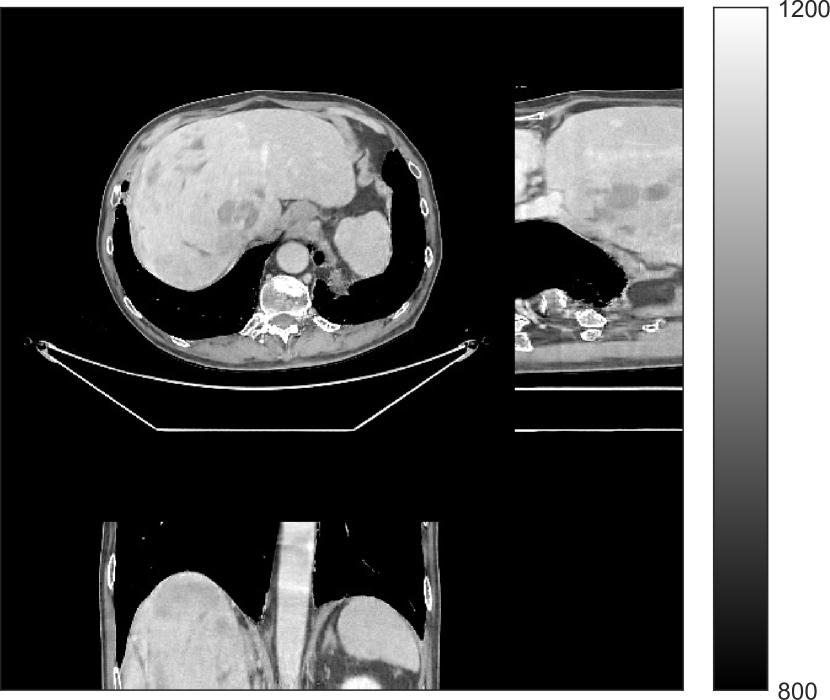

We used the pre-learned union of 15 square transforms from the XCAT phantom simulations to reconstruct the synthesized helical chest scan volume of size with mm and mm. The sinograms were of size . Since the clinical data is synthesized via the PWLS-ULTRA reconstruction, the noise model for this synthesized data is obscure, making it difficult to determine appropriate low-dose levels for such data. We tested the radiation dose of with an electronic noise variance the same as the XCAT phantom simulation, i.e., . The percentage of non-positive pre-log measurements for the synthesized clinical data in this case was around . Such non-positive values were replaced by for PWLS-based methods. Fig. 8(a) shows the “true” clinical image that was reconstructed from real clinical regular-dose sinogram using the PWLS-ULTRA method.

Similar to the XCAT phantom simulation, the initial image for both SPULTRA and PWLS-ULTRA was a reconstruction obtained using PWLS-EP. We set the regularizer parameter for PWLS-EP to to generate a smoother (with less noise) initial image, which led to good visual image equality for the SPULTRA and PWLS-ULTRA reconstructions. Since the optimization problem for PWLS-EP is strictly convex, we simply initialized PWLS-EP with a zero image. Fig. 8(b) shows the PWLS-EP reconstructed image for . We set the regularizer parameters for both PWLS-ULTRA and SPULTRA as , and .

V-B2 Reconstruction results for the synthesized clinical data

Fig. 9 shows three axial slices from the 3D reconstructions with SPULTRA and PWLS-ULTRA at : the middle slice (No. 67) and two slices located farther away from the center (No. 90 and No. 120). The image profiles along a horizontal line (shown in green) in the displayed slices are also shown in Fig. 9. The reconstructed slices using PWLS-ULTRA appear darker around the center compared to the “true” clinical image and the reconstructions with SPULTRA. This means PWLS-ULTRA produces a strong bias in the reconstruction. The bias can be observed more clearly in the profile plots: the pixel intensities for the SPULTRA reconstruction better follow those of the “true” clinical image, while those for the PWLS-ULTRA reconstruction are much worse than the “true” values. Moreover, SPULTRA achieves sharper rising and failing edges compared to PWLS-ULTRA. In other words, SPULTRA also achieves better resolution than PWLS-ULTRA. Fig. 9 also shows a zoomed-in ROI for each of the chosen slices, and highlights some small details with arrows. It is clear that in addition to reducing the bias, SPULTRA reconstructs image details better than PWLS-ULTRA.